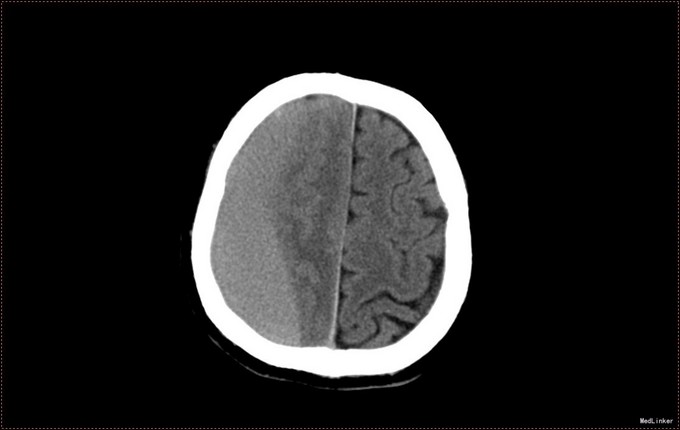

患者,男,53岁。以“左侧肢体疼痛伴无力1周”为主诉入院。患者1周前无明显诱因出现左侧肢体无力,伴酸痛,头部闷胀感,症状持续不缓解,于我院就诊,行头部CT及MR提示右侧顶枕叶硬膜下血肿。右侧额颞叶蛛网膜囊肿。患者为求进一步治疗,急诊以“硬膜下血肿”为诊断,收入病房。患者病来精神状态差,饮食睡眠可,二便可,体重无明显变化。否认近期头部外伤史。

入院查体:T:36.5℃ ,P:68次/分 ,BP:130/80mmHg , R:16次/分。步入病房,自主体位。神清语明,问答准确,查体合作,精神状态良好,定向力完整。粗测视野正常,双侧瞳孔等大正圆,D≈3.0mm,双侧眼球活动自如,对光反射灵敏。四肢活动自如,左侧肢体肌力V-级,右侧肢体肌力Ⅴ级,肌张力正常。深浅感觉检查未见异常。头CT及MR提示右侧颞极蛛网膜囊肿,右侧亚急性硬膜下血肿

患者诊断明确,完善术前检查行局麻右侧钻孔冲洗引流术,予常规治疗。术后3天拔管,复查头CT硬膜下血肿消失,但脑组织膨胀不良。患者左侧肢体肌力恢复正常,无头晕头沉症状,顺利出院。